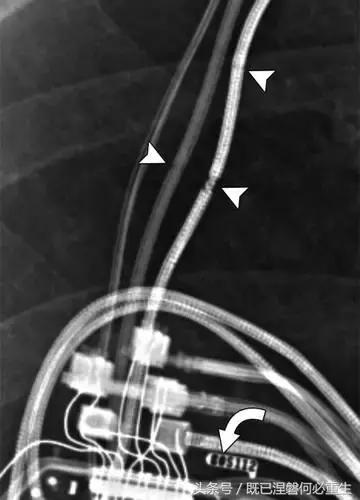

用于将导线的近端部分固定到胸壁的导线固定件可以模拟损伤。扎带是通常位于锁骨和发生器之间并且可以压接引线的套囊(图8A和8B)。熟悉这种外观和通常的射线透射束缚的位置可以防止错误报告磨损的线索。

图。 8A在两个不同患者中电极断裂的电极结合物的实例。

图。 8B在两个不同患者中电极断裂的电极结合物的实例。